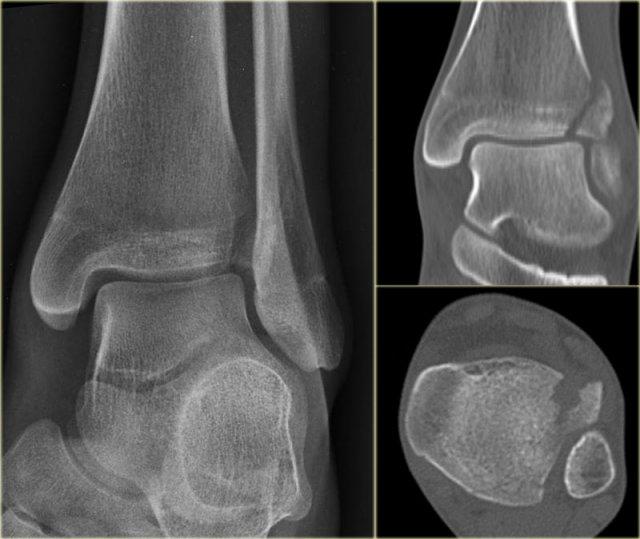

Đây là hình ảnh của một ca bệnh cực kỳ khó.

Bệnh nhân nữ bị bong gân cổ chân và đau cả hai bên trong và ngoài.

Bệnh nhân được bác sĩ đa khoa chuyển đến khoa Chẩn đoán Hình ảnh.

Kỹ thuật viên chụp các tư thế chuẩn gồm thẳng (AP), Mortise và nghiêng, sau đó trình bày cho bác sĩ X-quang, người đã khá băn khoăn khi đọc phim.

Hãy đọc hình ảnh trước, sau đó tiếp tục đọc phần giải thích.

Các dấu hiệu bao gồm:

-

Phù nề phần mềm cả hai bên trong và ngoài (mũi tên đỏ).

Đặc biệt, phù nề phía trong nên gợi ý khả năng chấn thương xoay ngoài – sấp (Weber C). - Đường thấu quang trên tư thế Mortise (mũi tên đen) và tư thế nghiêng. Dấu hiệu này nên gợi ý gãy tertius.

Bác sĩ X-quang quyết định chỉ định CT trước để xác định xem có thực sự có gãy tertius hay không.

Tiếp tục xem hình ảnh CT và bạn sẽ ngạc nhiên.

Hãy cuộn qua các lát cắt.

Thật đáng ngạc nhiên khi một mảnh tertius lớn như vậy lại rất khó nhìn thấy trên phim X-quang.

Cũng lưu ý phù nề phần mềm phía trong gợi ý đứt dây chằng bên trong (mũi tên).

Bạn có thể đoán được đây là loại chấn thương gì không?

Phù nề phần mềm phía trong và gãy tertius đều là dấu hiệu của chấn thương Weber C hoặc chấn thương xoay ngoài – sấp.

Do không thấy gãy xương mác trên phim X-quang cổ chân, phải có gãy xương mác cao.

Khi khám lâm sàng, có phù nề nhẹ phía trong và mặc dù bệnh nhân không than đau ở vùng cao hơn của cẳng chân, vẫn có điểm đau khi ấn vào xương mác.

Vị trí này được đánh dấu và phát hiện đường gãy.

Ca bệnh này minh họa tầm quan trọng của phù nề phần mềm phía trong cũng như dấu hiệu gãy tertius.

Theo phân loại Lauge Hansen, chúng ta có thể kết luận rằng bệnh nhân này đầu tiên bị đứt dây chằng bên trong (giai đoạn 1), tiếp theo là đứt dây chằng chày mác trước (giai đoạn 2), gãy xương mác cao (giai đoạn 3) và cuối cùng là bong mắt cá sau, tức là chấn thương xoay ngoài – sấp (PE) giai đoạn 4.

Trong phẫu thuật, cổ chân được xác định là không vững và vít cố định khớp chày mác đã được đặt vào.

Có chỉ định cố định gãy mắt cá sau vì mảnh gãy chiếm hơn 25% diện khớp của đầu dưới xương chày.